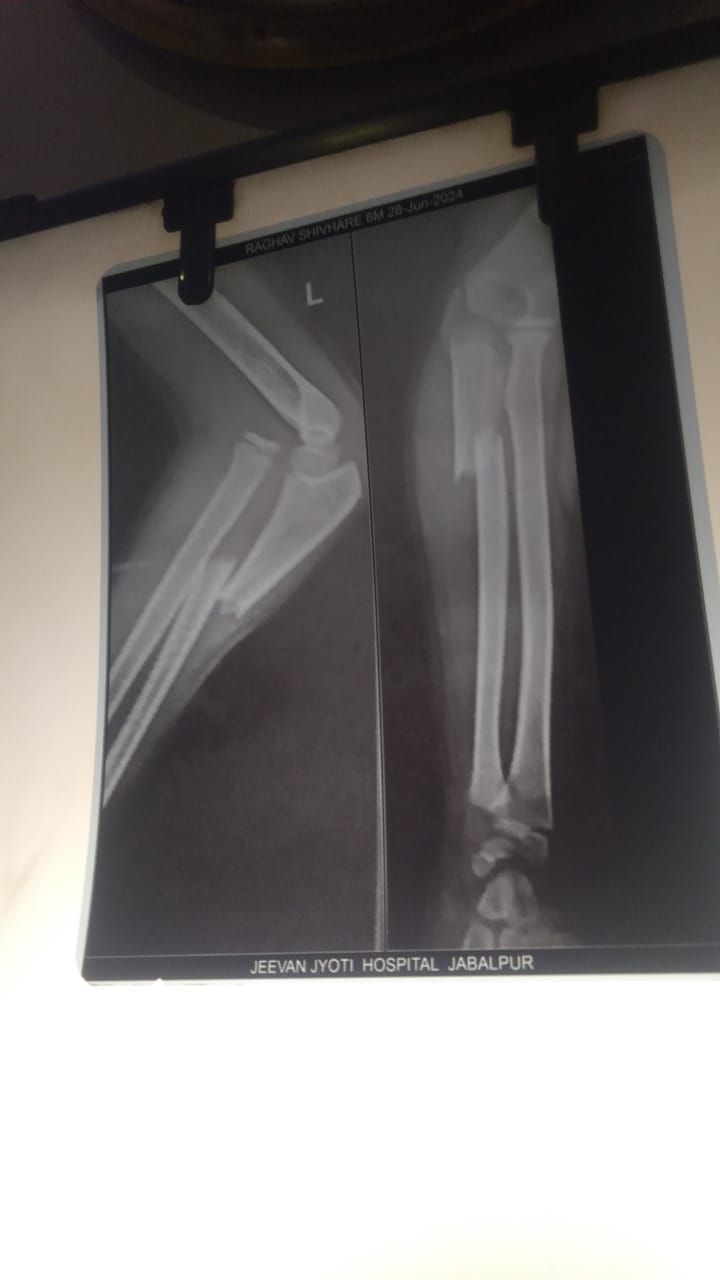

Mr. Sunil shivhare (father of baby) work at a ration shop. He is the only sole-earner in the family managing daily livelihood and hardly earns 7000/- per month. The baby’s mother is a house wife. One day Raghav (baby of sunil shivhare) met with an accident while playing on the road and his hand got badly injured and the bone got broken and now he needs an operation to recover.

Baby of Mr. Sunil Shivhare is a 6 year old child admitted in Jeevan Jyoti Hospital in jabalpur. The treatment duration is of 40 days. We humbly request you to please come forward with a supporting hand and save this bright future of the baby Raghav.